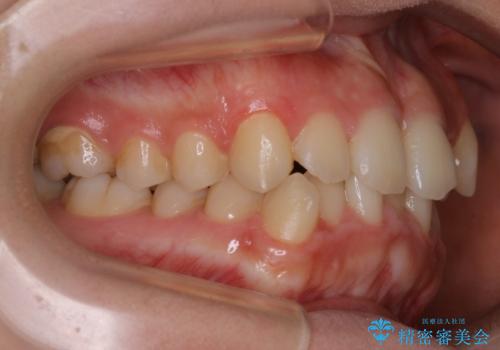

- 上の前歯のすきっ歯と下の前歯のガタつきを主訴にご来院されました。

噛み合わせの改善も同時に進めつつ、主訴の部分も効率的に治していくためマウスピース装置でゴムかけを行いながら治療を進めていきました。